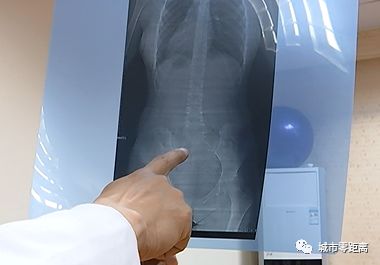

经过医生初步判定,

零距离记者有轻微的脊柱侧弯的症状。

市中医院脊柱科主任吴俊哲说,

在中山,脊柱侧弯的发病率高于全国